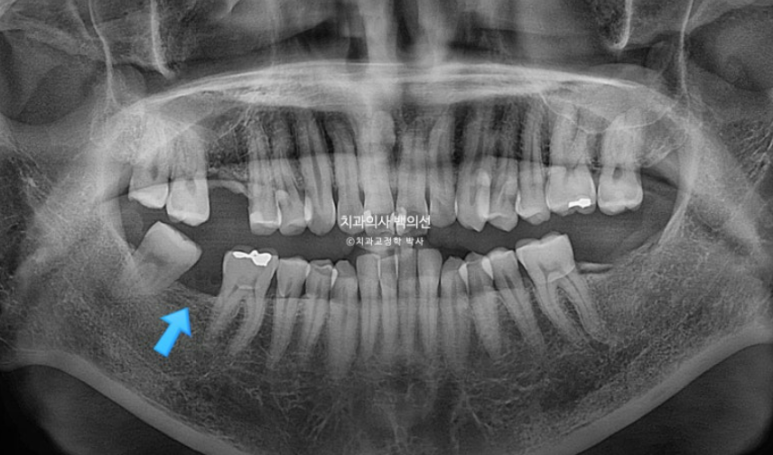

특히 파란 화살표 공간은 뒤 사랑니가 앞으로 많이 쓰러져서 임플란트가 힘든 상황입니다.

이렇게 좁아져버린 임플란트 공간을 회복하기 위해 쓰러지고 내려온 주변치아들을 정돈하는 교정을 보철교정이라고 합니다.

좁아진 공간과 쓰러진 사랑니는 파노라마 엑스레이에서 확인됩니다.

이런 경우 사랑니를 빼버리면 간단하게 해결이 되지만, 이미 상해서 빠진 이가 많은 상태인데다가 사랑니가 잘 나와 대합치과 교합까지 잘 되는 상태라, 사랑니를 최대한 보존해서 쓰기로 합니다.